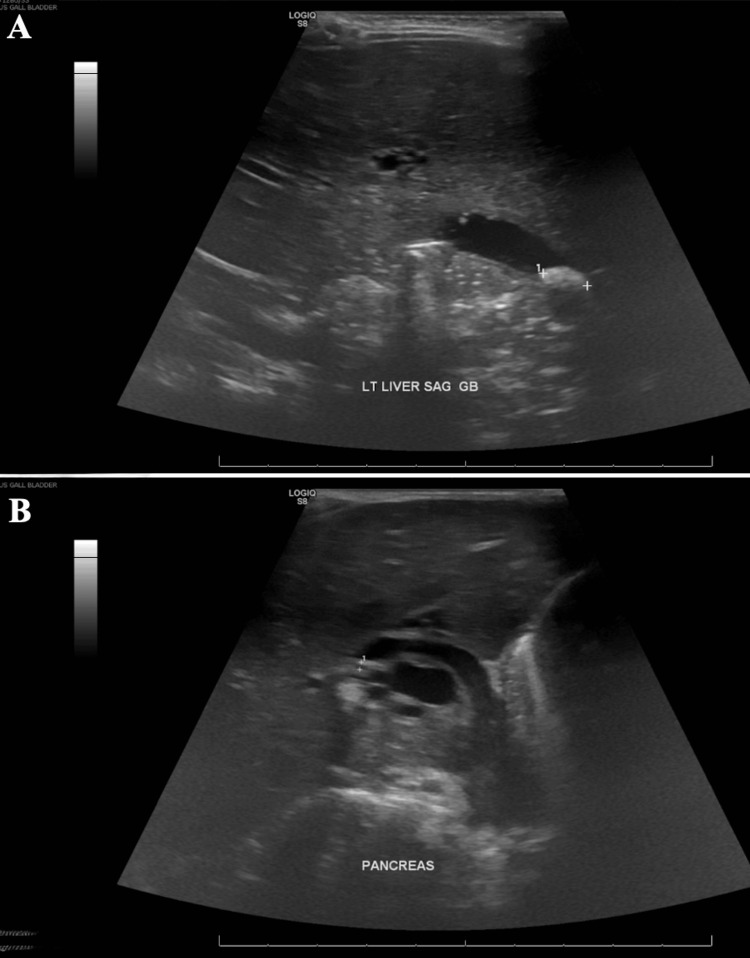

Due to a lack of pediatric interventional gastroenterologists and appropriate equipment at our institution, efforts to transfer the patient to an outside facility with the capability to perform endoscopic retrograde cholangiopancreatography (ERCP) in pediatric patients were started. Since admission, the patient had significant clinical improvement, laboratory abnormalities resolved, and pain was well controlled. Repeat ultrasound (Figure 3) had persistent biliary dilation with cholelithiasis. Due to a lack of availability of outside facilities with ERCP and patient clinical improvement, a decision was made to continue medical management. The patient was cleared for discharge on ursodiol and amoxicillin-clavulanate and close follow-up with pediatrician, pediatric surgeon, and pediatric gastroenterologist.